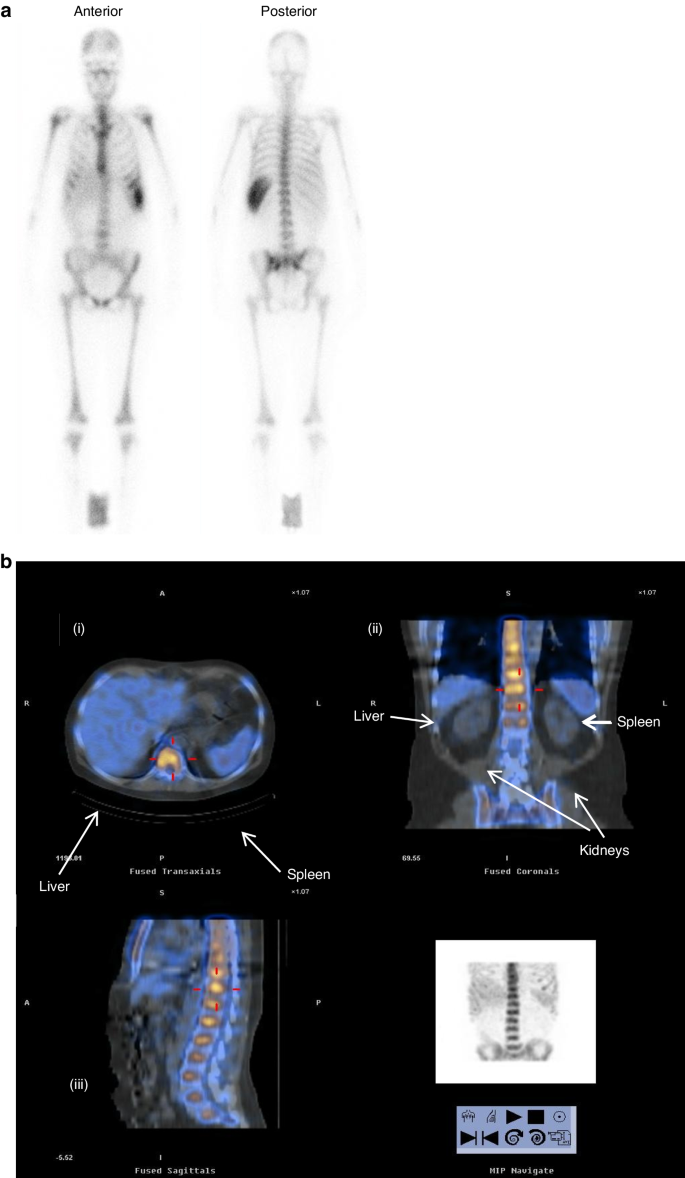

Blood 111In activity displayed similar biphasic retention in all patients, consistent with the sum of two exponential functions. In each patient, an initial rapid fall in blood 111In activity occurred within 2 h, followed by a slower decrease over 5–10 h (Fig. 1). After 24 h, the decrease in activity was markedly slower, approximating the physical half-life of the isotope and most of the radiation was located in the red marrow as indicated by whole-body planar gamma images (Fig. 2a) and SPECT(-CT) (Fig. 2b). From the early time-activity plots, the mean derived T½ alpha 2.06 ± 0.96 h (range 0.9–3.4), T½ beta 6.0 ± 3.2 h (range 4.0–9.0).

a Whole-body gamma-camera image showing distribution of 111In-anti-CD66 monoclonal antibody. b Superimposed SPECT gamma radiation (coloured) and CT images (grey scale). (i) Cross-section showing strong gamma radiation signal in L3 vertebral body (yellow), low in liver and spleen (blue) and undetectable in muscle, bowel. (ii) Coronal section image showing strong gamma radiation signal in vertebrae and pelvis (yellow), low in liver and spleen (blue) and very low in kidneys (grey scale image of CT). (iii) Sagittal image showing high gamma signal (yellow) in vertebral bodies, sternum and virtually none in other organs.

Thirty patients received 111In-anti-CD66. In the first cohort, one patient failed dosimetry with red marrow:liver ratio < 2:1 and was excluded from the study. Within the trial, 29 patients received 90Y-anti-CD66 at infused activity levels of 5, 10, 25 and 37.5 MBq 90Y per kilogram body weight, activity ranged from 229 to 2758 MBq, determined by patient weight and treatment cohort. In Table 2, the mean absorbed radiation dose to red marrow, spleen, liver, lungs and kidneys are expressed as milliGray per megaBequerel (mGy/MBq) of infused 90Y-anti-CD66 and the mean total organ doses are in Gy. The mean (±1 SD, range) estimated radiation dose delivered per unit infused radiation activity expressed as mGy/MBq were marrow 10.2 (±3.4, 6.5–16.2), liver 2.4 (±1.1, 1.4–5.6), spleen 9.0 (±3.9, 3.3–20.3), renal 0.6 (±0.4, 0.4–1.2), lungs 0.9 (±0.5, 0.5–1.8) and whole body 0.4 (±0.1, 0.2–0.6). The uptake of radiolabelled antibody by red marrow showed a high degree of consistency between patients. The mean red marrow to liver ratio was 4.3:1, estimated radiation doses to lung, kidneys, muscle and gut were considerably lower than to red marrow, shown graphically in Fig. 3. In most patients, the distribution of radiation was similar with marked uptake in the axial skeleton, ribs, sternum, pelvis, base of skull and proximal ends of the femur and humerus (Fig. 2a), consistent with red marrow distribution in adults.